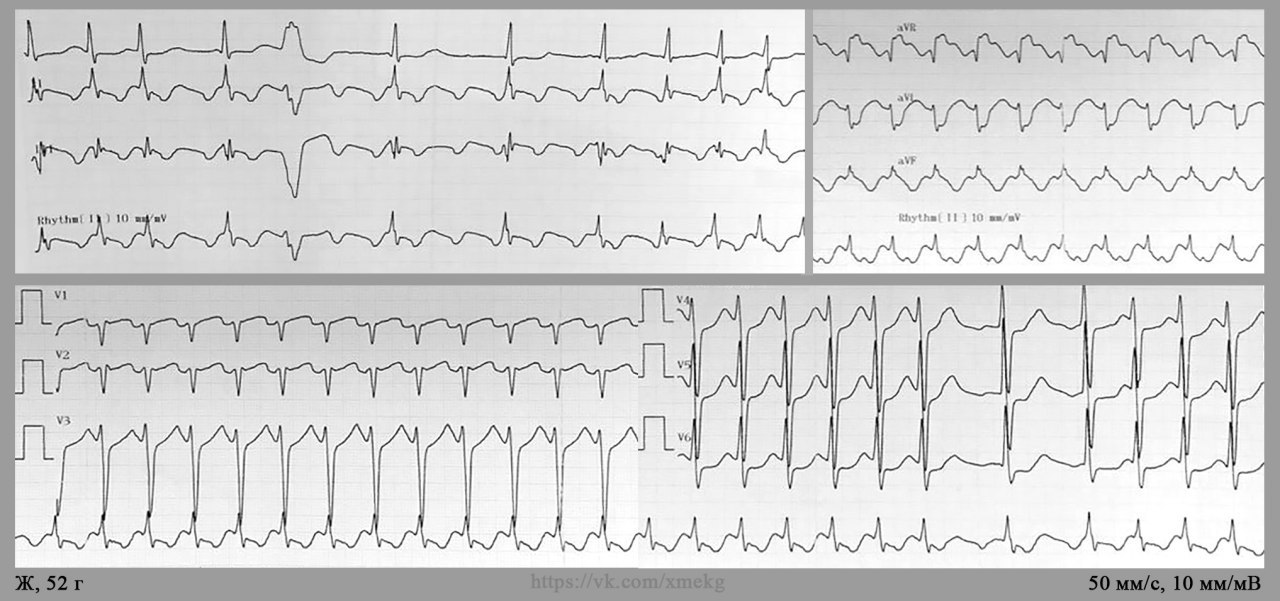

Случай от коллег: трепетания предсердий с проведением 1:1 у женщины 52х лет. Подробности, к сожалению, не известны. Снято 2 плёнки с небольшой разницей во времени. На первой плёнке наблюдается регулярная наджелудочковая тахикардия частотой 230 в 1 мин, и достоверно судить о её механизме затруднительно. Однако на второй плёнке отчётливо видны небольшие паузы в ритме с явными волнами трепетания с проведением 2:1-3:1 (например, после желудочковой экстрасистолы в отведениях I, II, III)